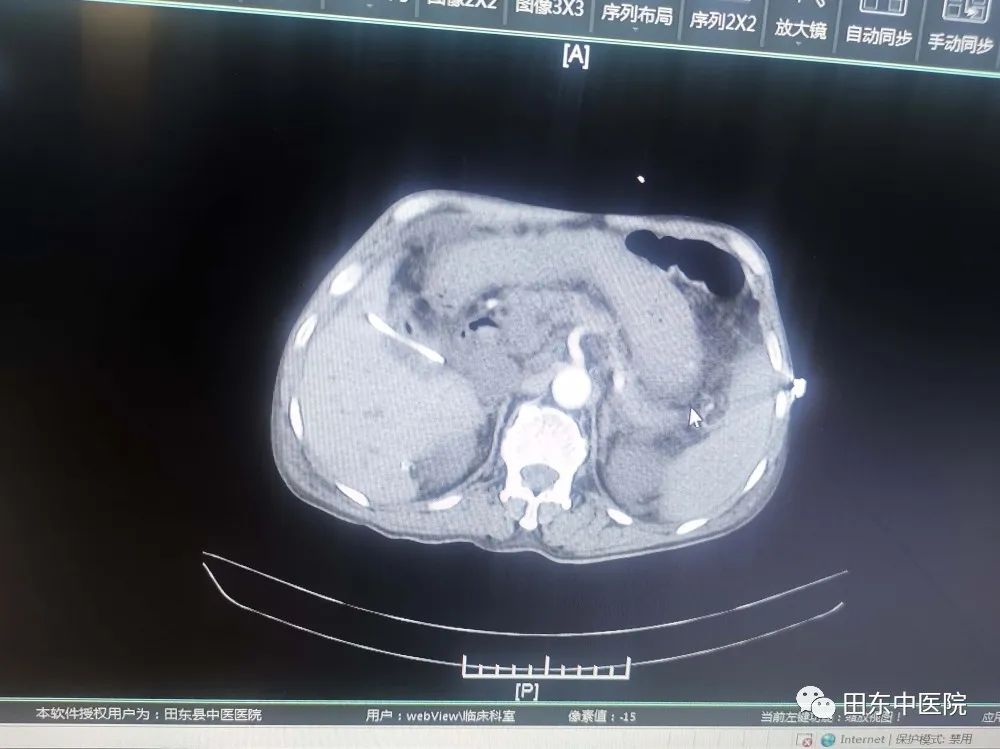

患者入院时有腹部剧痛、黄疸、寒战高热等症状,通过腹部CT增强、磁共振增强+胆道水成像等检查后,发现患者有:1、急性梗阻性化脓性胆管炎 2、脓毒血症 3、感染性休克 4、梗阻性黄疸 5、腹膜炎等多项急危重症,病情岌岌危重,急诊行PTCD引流术,经积极抗感染、扩容、抗休克、护肝退黄等措施把患者从死亡边缘抢救过来。